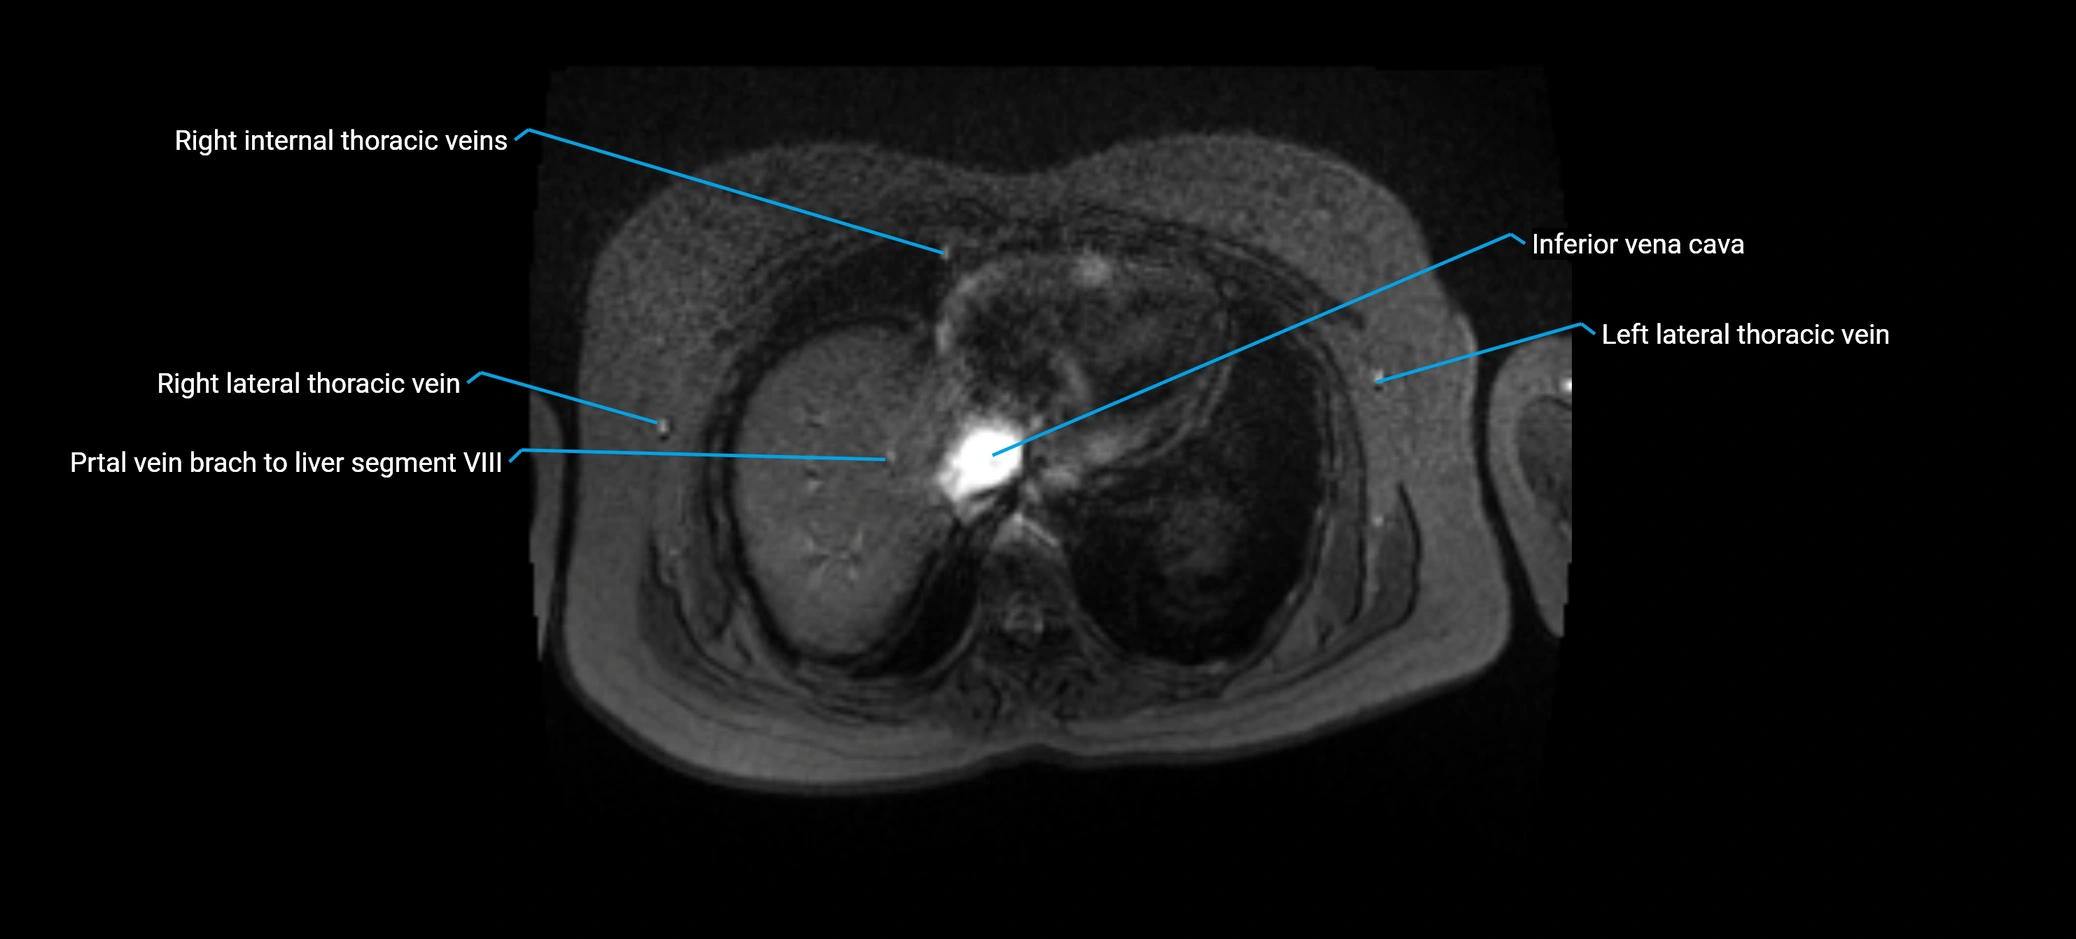

MRI image

image